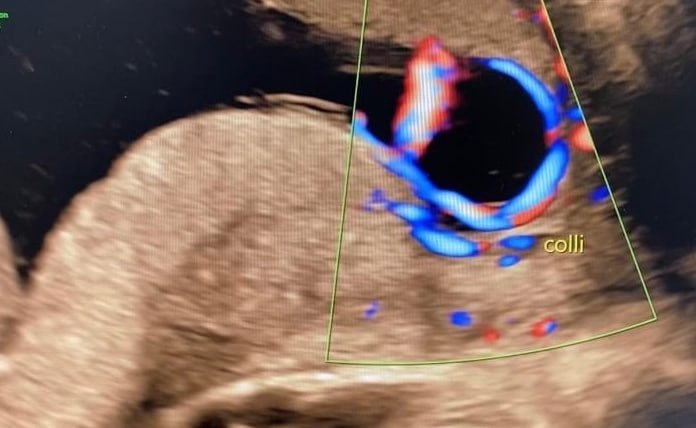

Чтобы вовремя обнаружить у себя vasa praevia, необходимо проходить диагностику с помощью УЗИ и трансвагинального осмотра.

«Важно тщательно оценивать место прикрепления пуповины и риск оболочечного расположения сосудов даже при прикреплении к плаценте», — рассказал Никонов.